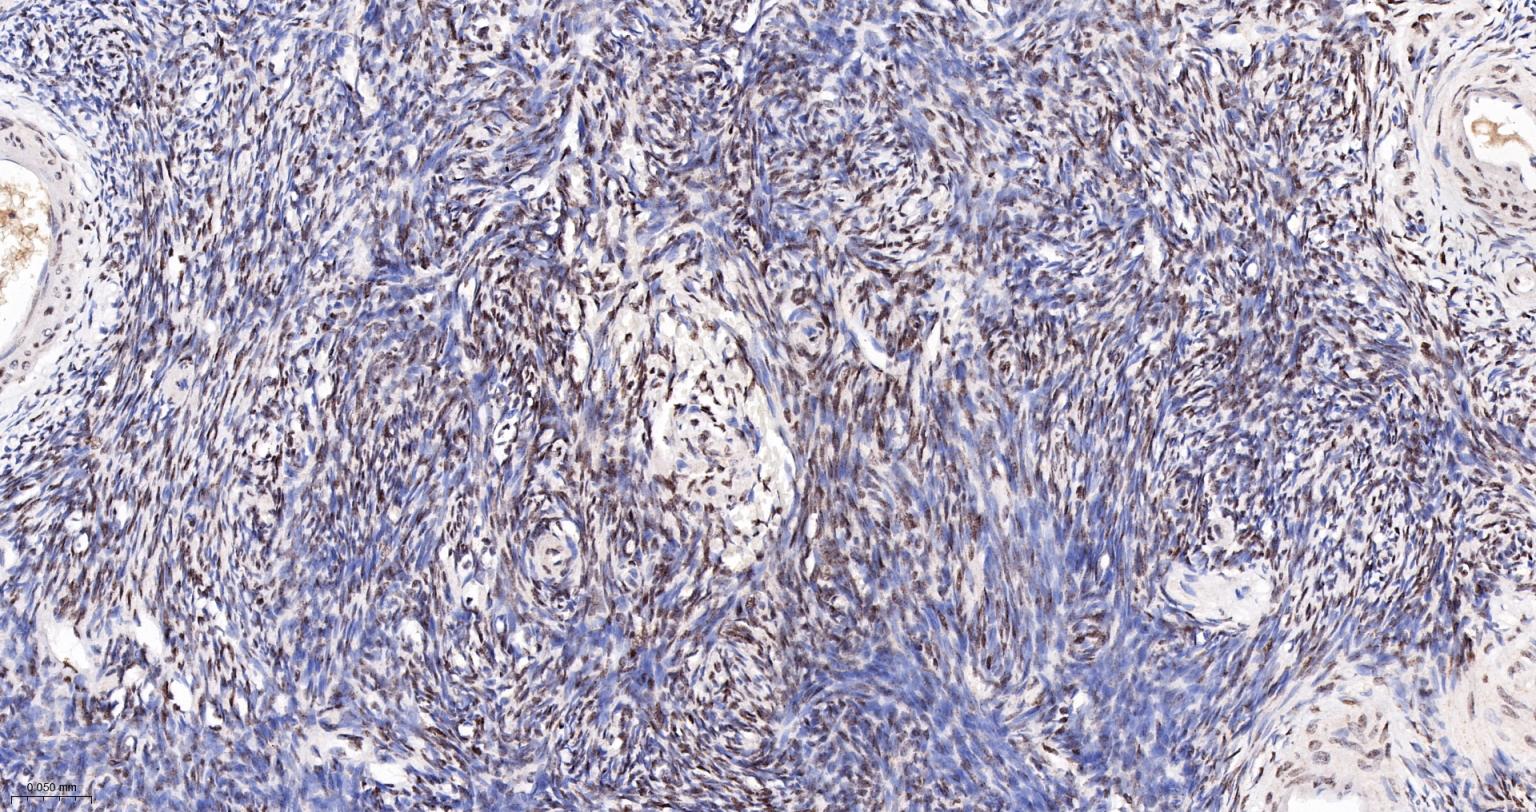

Paraformaldehyde-fixed, paraffin embedded Human Glioma; Antigen retrieval by boiling in sodium citrate buffer (pH6.0) for 15 min; The section was incubated with COUP-TF1 Monoclonal Antibody, Unconjugated (bsm-61615R) at 1:200 overnight at 4°C, followed by conjugation to the bs-0295G-HRP and DAB (C-0010) staining.